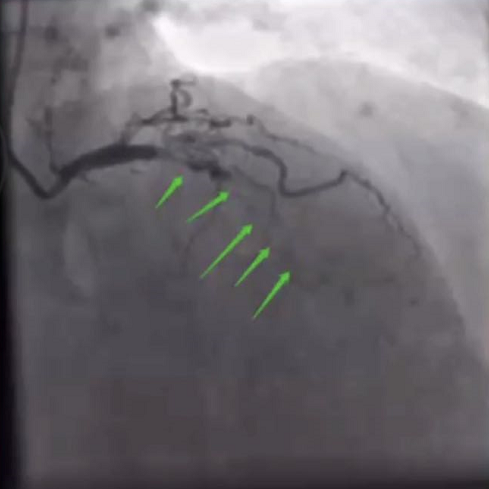

山西省心血管病医院暴清波教授结合病例分享了小球囊在高阻病变中的应用。首先是一例60岁的ACS病例,既往有RCA支架植入病史,本次入院冠脉造影提示RCA自近段闭塞。手术过程中,先后使用Filder XT-A导丝、Gaia 2导丝,成功通过闭塞段,但mini trek小球囊及Goodman小球囊均无法通过,闭塞段阻力较高,最终通过Firefighter™球囊锚定技术将球囊送入闭塞段以远。

RCA CTO病变

RCA支架植入后

西安交通大学第一附属医院郭宁教授认为对于这种高阻力的CTO病变,球囊锚定技术及小球囊掘进技术对于开辟管腔通道有重要价值,尤其是导丝在闭塞段走行不明确时,结合个人应用体会而言,使用Firefighter™球囊一点点跟进,可以达到“滴水穿石”、逐步撬开坚硬病变的效果。